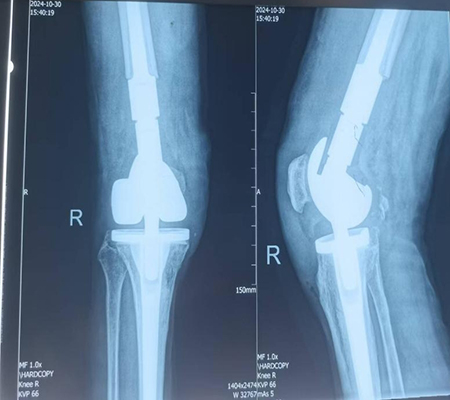

膝關(guān)節(jié)置換術(shù)后假體周圍骨折,假體松動(dòng)

手術(shù)由骨科專家許立新主任親自主刀,在手麻科醫(yī)護(hù)人員的全力配合下,順利開展。手術(shù)過程中,發(fā)現(xiàn)膝關(guān)節(jié)假體徹底松動(dòng),脛骨假體也發(fā)生了松動(dòng),這再次證實(shí)了術(shù)前計(jì)劃的合理性,去除松動(dòng)假體后,安裝特制腫瘤膝關(guān)節(jié),手術(shù)過程非常順利,僅用時(shí)86分鐘。

膝關(guān)節(jié)置換術(shù)后假體周圍骨折特殊假體返修術(shù)后